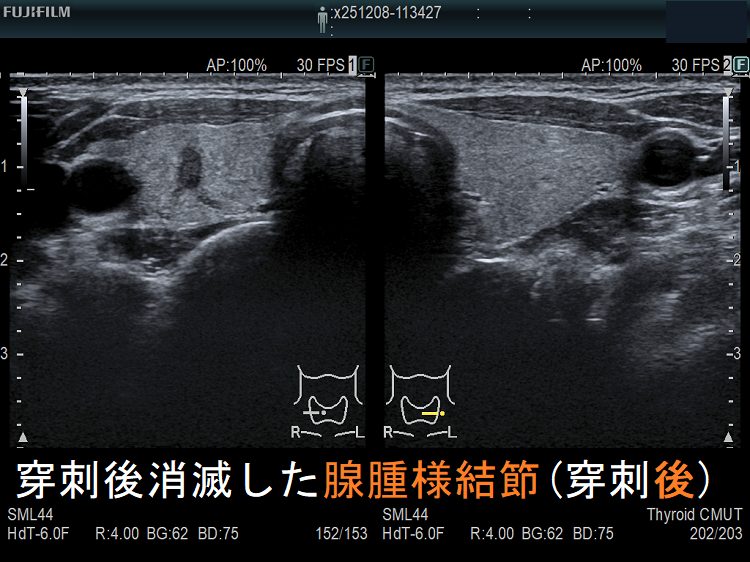

穿刺細胞診後内部融解

ケース①

ケース②